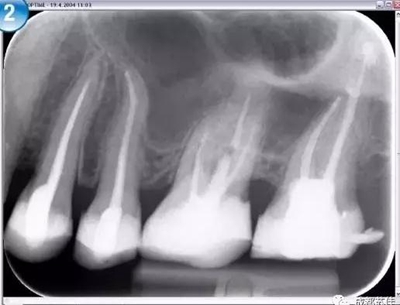

空間分辨率最高可達16.7lp/mm,16位(65,636)的灰度,能夠可靠的分辨出D1級別的齲損及細小至ISO 06 級別的根管器械。